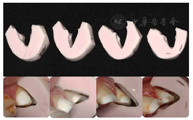

首先对上颌牙进行牙体预备,将诊断蜡型的硅橡胶成型阴模切片,指导前牙预备。牙体预备完成后,制取硅橡胶印模,灌制工作模型。于备牙过程中逐步去除

垫、制取颌位记录以转移咬合关系,使用成型阴模加临时冠桥树脂材料将蜡型Mock up至口内,作为临时修复体(图24,图25,图26,图27,图28,图29,图30,图31)。